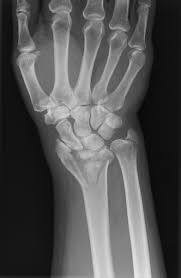

Las fracturas en los pequeños huesos de la mano podrían sanar bien siempre y cuando el daño no sea muy grave. Una quebradura de muñeca es una fractura o fisura en uno o más huesos de la muñeca. 2012 Descripción Educación Común y modalidades Educación Especial y Educación de Jóvenes y Adultos.

Sin embargo podría haber un daño a los nervios lo cual afectaría la funcionalidad. Cuánto tiempo debes evitar. Generalmente el rompimiento se encuentra aproximadamente una pulgada 25 centímetros por encima del lugar en el que el hueso se une a la muñeca.

Cuánto tiempo dura la rehabilitacion de. El extremo inferior del hueso se rompe bastante cerca del lugar donde se conecta con los huesos que pertenecen a la mano al lado del pulgar de la muñeca. Una quebradura de muñeca es una fractura o fisura en uno o más huesos de la muñeca.

Una fractura ocurre cuando hay una rotura o fisura en uno o más de los huesos. Este tipo de fractura se puede producir de muchas maneras diferentes. Las lesiones más frecuentes se producen en la muñeca cuando las personas intentan sujetarse durante una caída y cuando caen al suelo con la mano extendida.